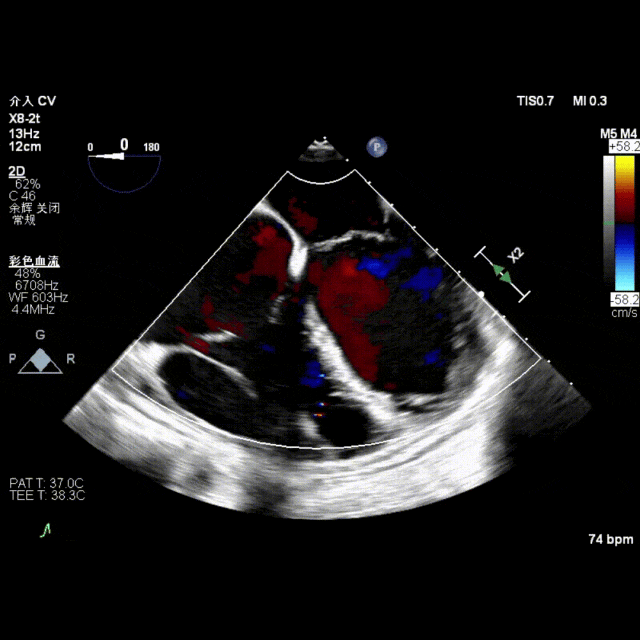

术后即刻超声